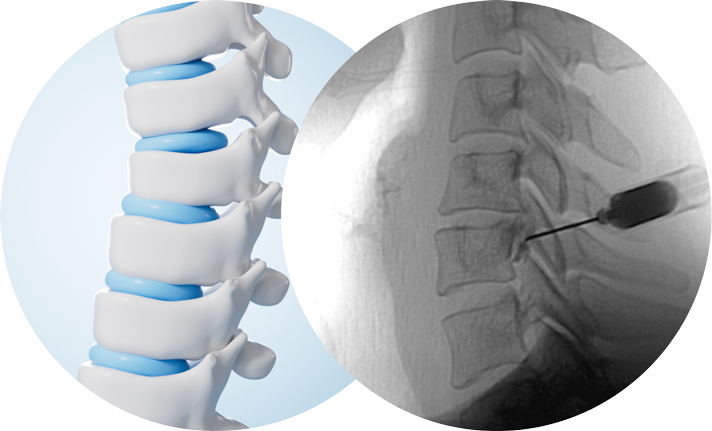

특수영상장비를 통해 병변 부위를 직접 확인하면서 염증이 생긴 부위에 항염증제나 국소마취제가 포함되어

있는 약물을 주입하여 염증을 제거하고 통증 전달을 차단하는 주사치료를 말합니다. 신경을 누르며 염증을

유발시키는 디스크에 많이 사용되기도 합니다.